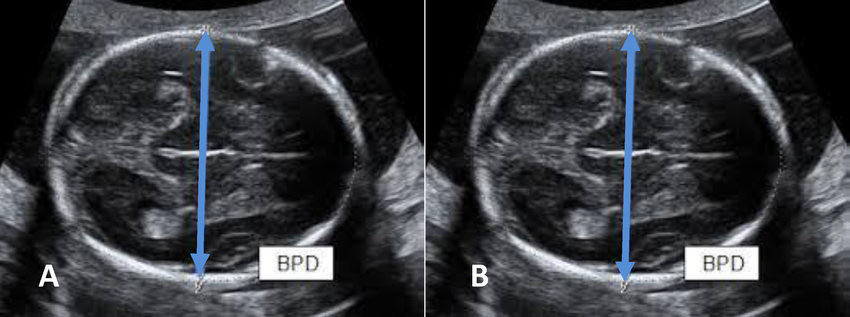

Đường kính lưỡng đỉnh (BPD), hay còn gọi là Biparietal Diameter trong tiếng Anh, là số đo quan trọng được thực hiện trong quá trình siêu âm thai. Đây là đường kính lớn nhất của hộp sọ thai nhi, đo từ trán đến sau gáy.

Trong siêu âm thai, BPD là chỉ số đường kính lưỡng đỉnh, được đo ở mặt cắt lớn nhất (tính từ trán ra sau gáy) của hộp sọ của thai nhi hoặc có thể hiểu là đường kính đầu của em bé, giúp ước lượng cân nặng, tuổi thai cũng như đánh giá sự phát triển của thai nhi.

Đường kính lưỡng đỉnh (BPD) là đường cắt ngang hộp sọ của thai nhi